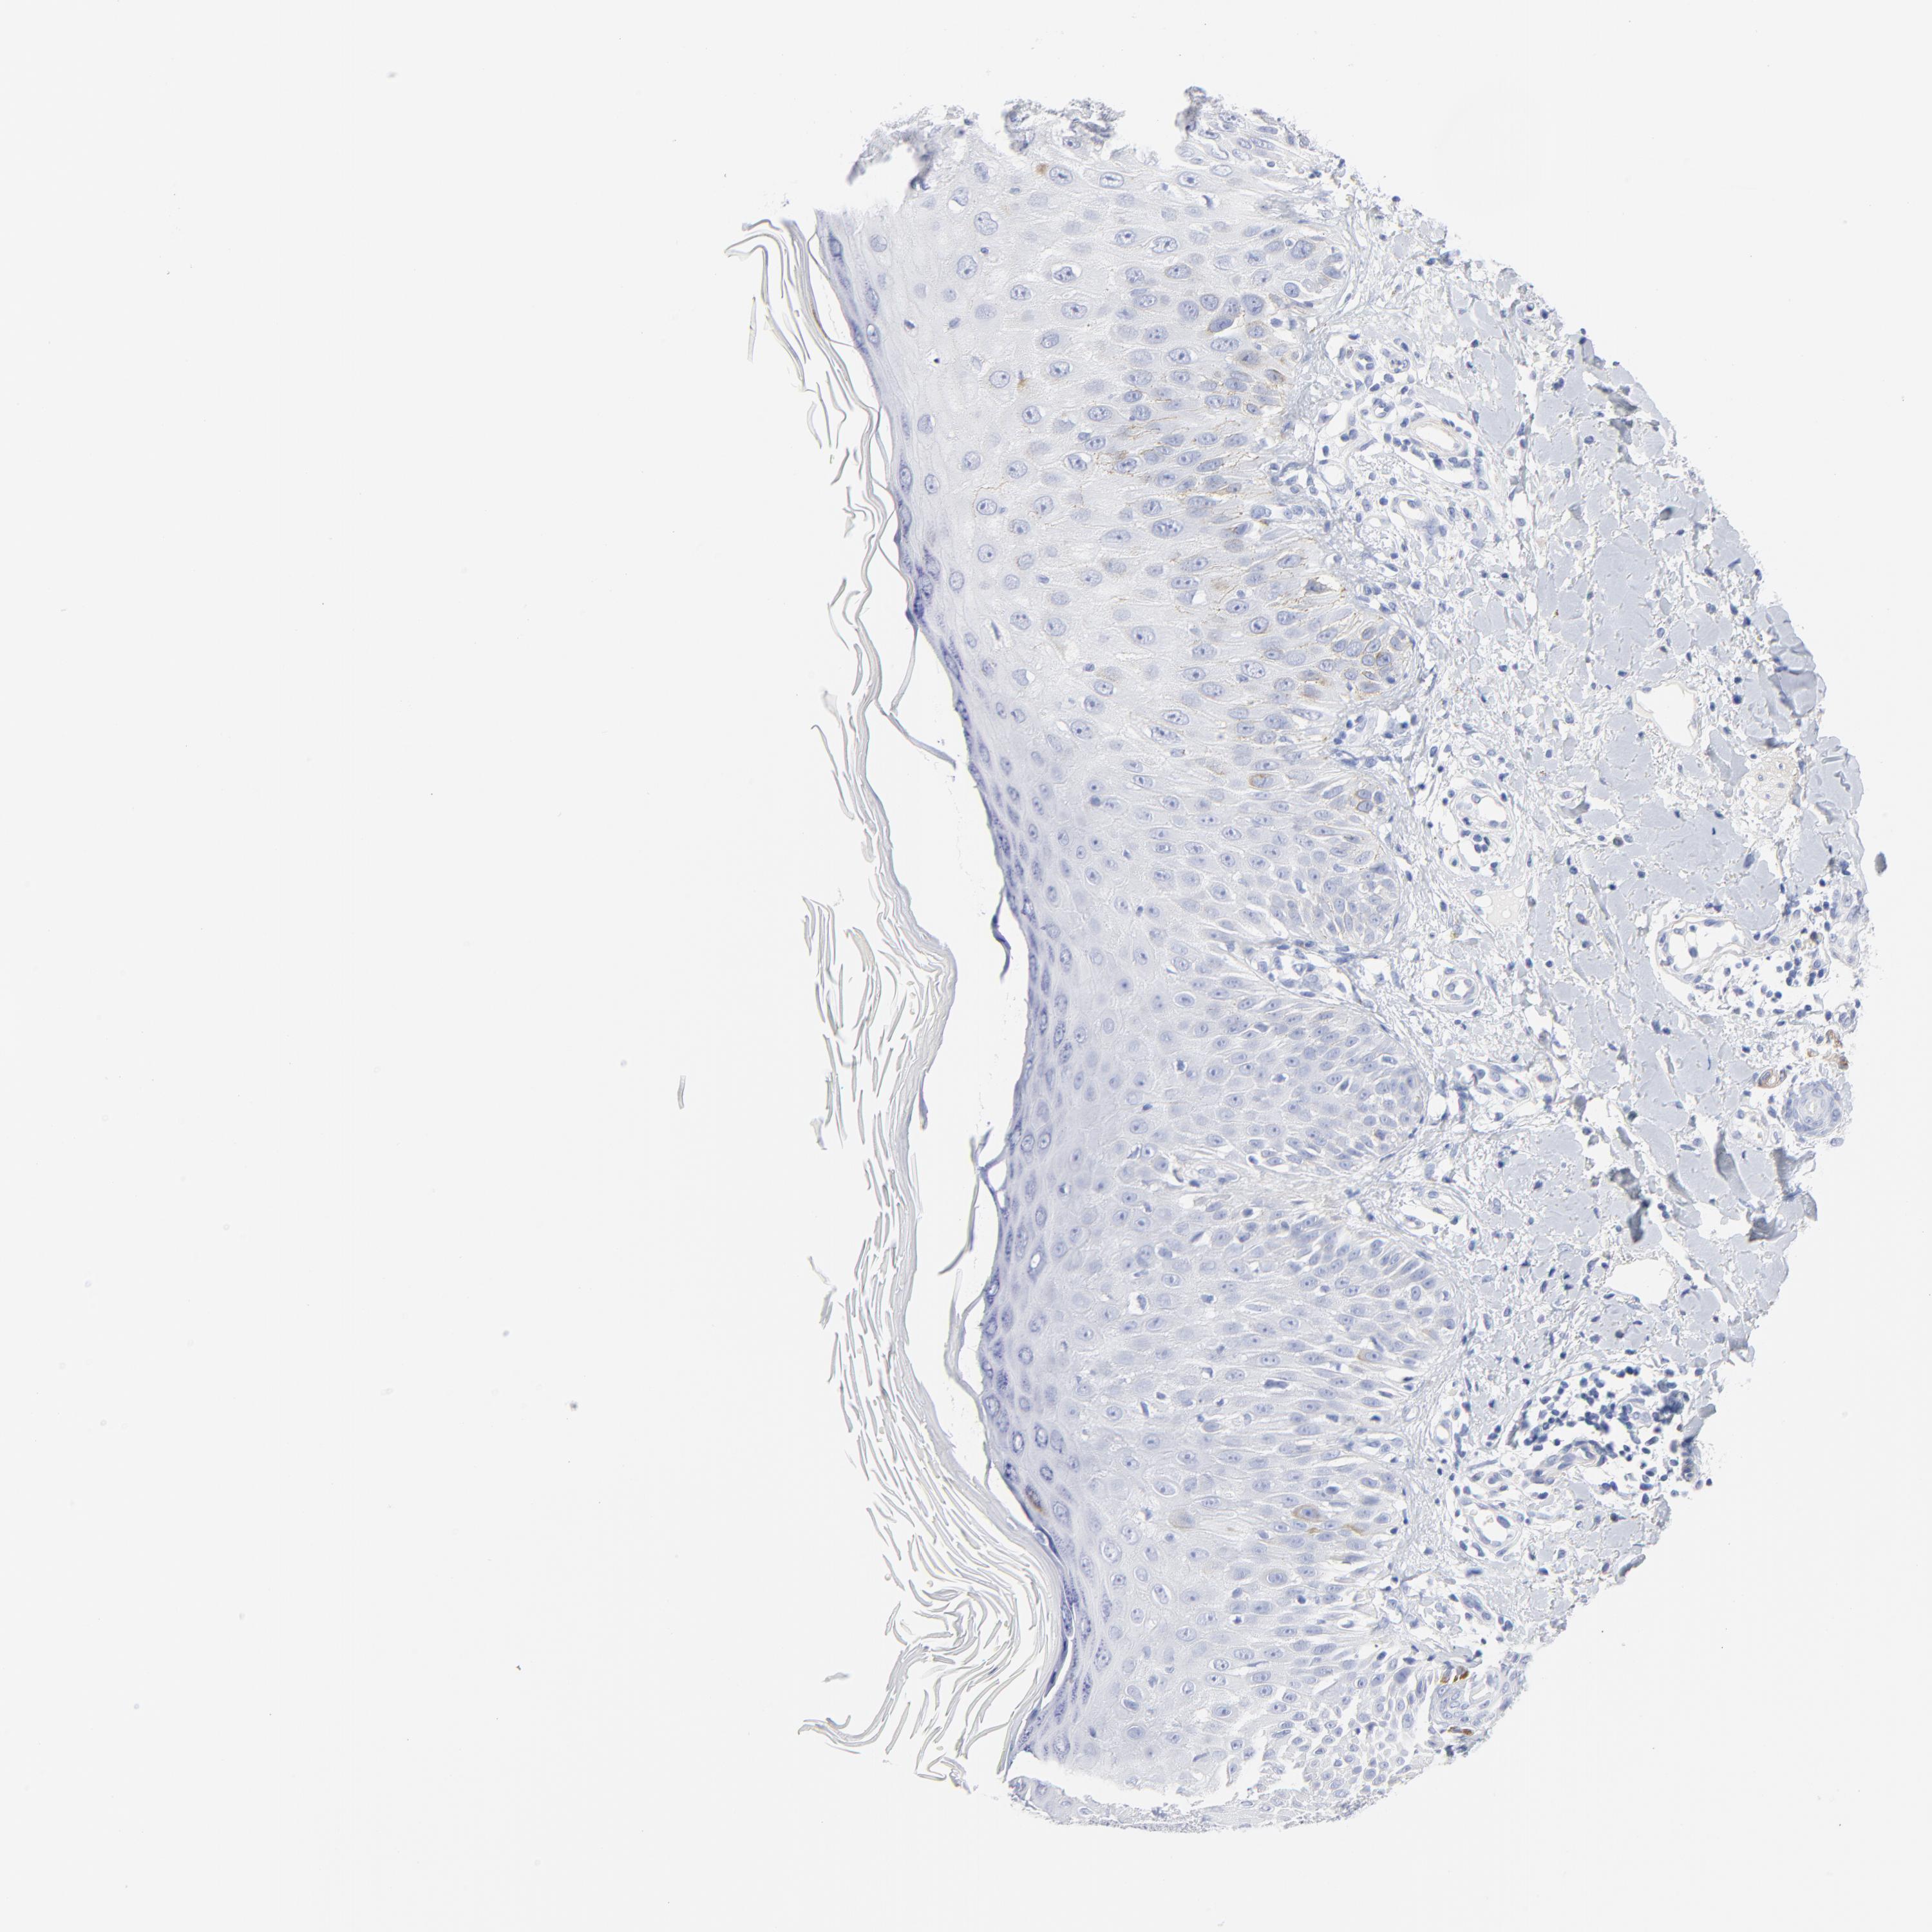

SKIN CANCER - Protein expressioni

A mouse-over function shows sample information and annotation data. Click on an image to view it in a full screen mode. Samples can be filtered based on level of antibody staining by selecting one or several of the following categories: high, medium, low and not detected. The assay and annotation is described here.

Antibody stainingi

Antibody staining in the annotated cell types in the current human tissue is reported as not detected, low, medium, or high, based on conventional immunohistochemistry profiling in selected tissues. This score is based on the combination of the staining intensity and fraction of stained cells.

Each image is clickable and will lead to virtual microscopy that enables deeper exploration of all samples and also displays staining intensity scores, fraction scores and subcellular localization as well as patient and tissue information for each sample.

Antibody HPA003596

Squamous cell carcinoma, NOS

Basal cell carcinoma